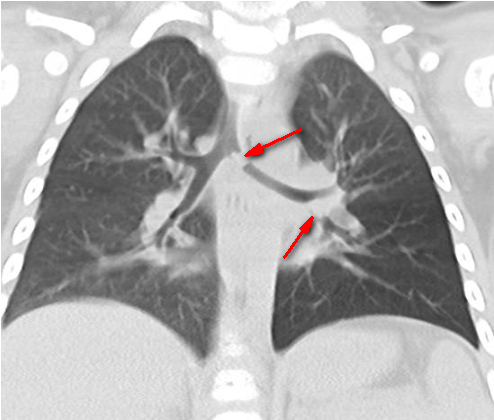

柳州市工人医院儿科主任劳金泉接诊后,考虑是气道内存在异物,在做了CT后,证实患儿气道内存在异物,医护人员立即展开抢救。

CT片显示有异物

气管镜伸入气管时,可见一颗碎骨头将左主支气管部分堵住。